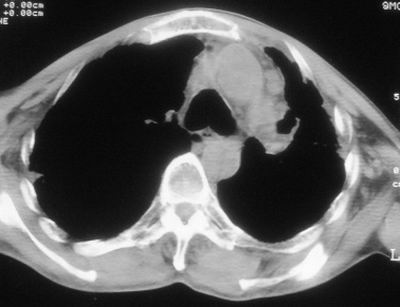

标题: CT11864:男,47岁,反复咳嗽、咯痰、咯血3年,请分析. [打印本页]

患者,男,47岁,反复咳嗽、咯痰、咯血3年,再发5天。痰培养未找到真菌、抗酸杆菌、癌细胞。

左肺上叶体积明显缩小,其内见多发透光区,纵隔向左侧移位,左肺下叶多发班片状病灶,边界模糊,1左肺上叶先天肺发育不全,2左肺下叶肺炎,

左肺上叶结核伴肺纤维化,纵隔移位,左肺下叶感染性病变,建议抗炎抗结核后复查,双肺气肿.

考虑:左肺慢纤伴霉菌球形成、双肺全小叶型肺气肿。

1)考虑为:左肺上叶肺结核(空洞形成),伴左下肺感染;不排除霉菌感染可能。2)肺气肿。

左肺上叶结核伴肺纤维化空洞形成并左肺下叶感染,纵隔牵拉移位,建议作进一步检查排除左侧肺霉菌感染可能。